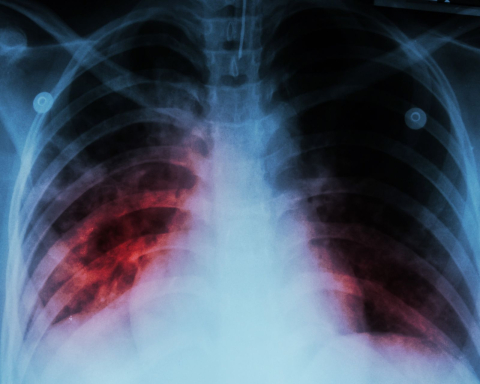

A chest x-ray shows alveolar infiltration at both lung due to mycobacterium tuberculosis infection